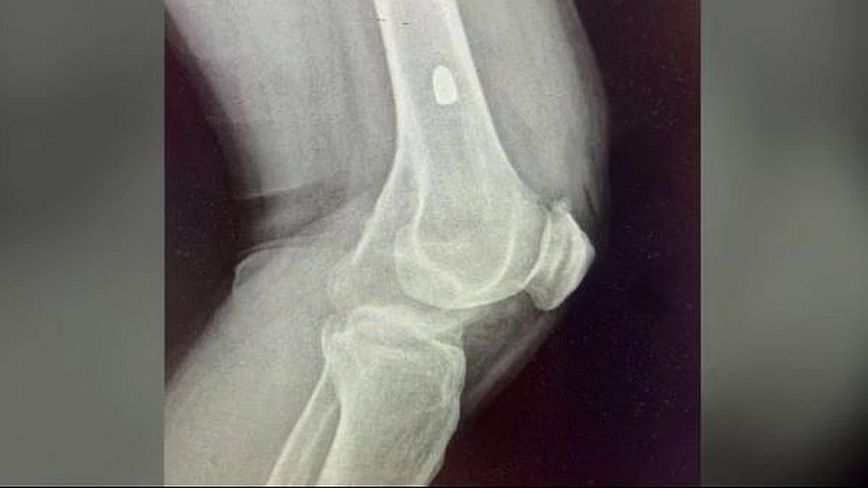

Το MEGA δημοσίευσε και φωτογραφία που δείχνει τη σφαίρα των εννέα χιλιοστών μέσα στο σώμα του θύματος.

Οι γιατροί την αφαίρεσαν και την έστειλαν στα εγκληματολογικά εργαστήρια της ΕΛ.ΑΣ.